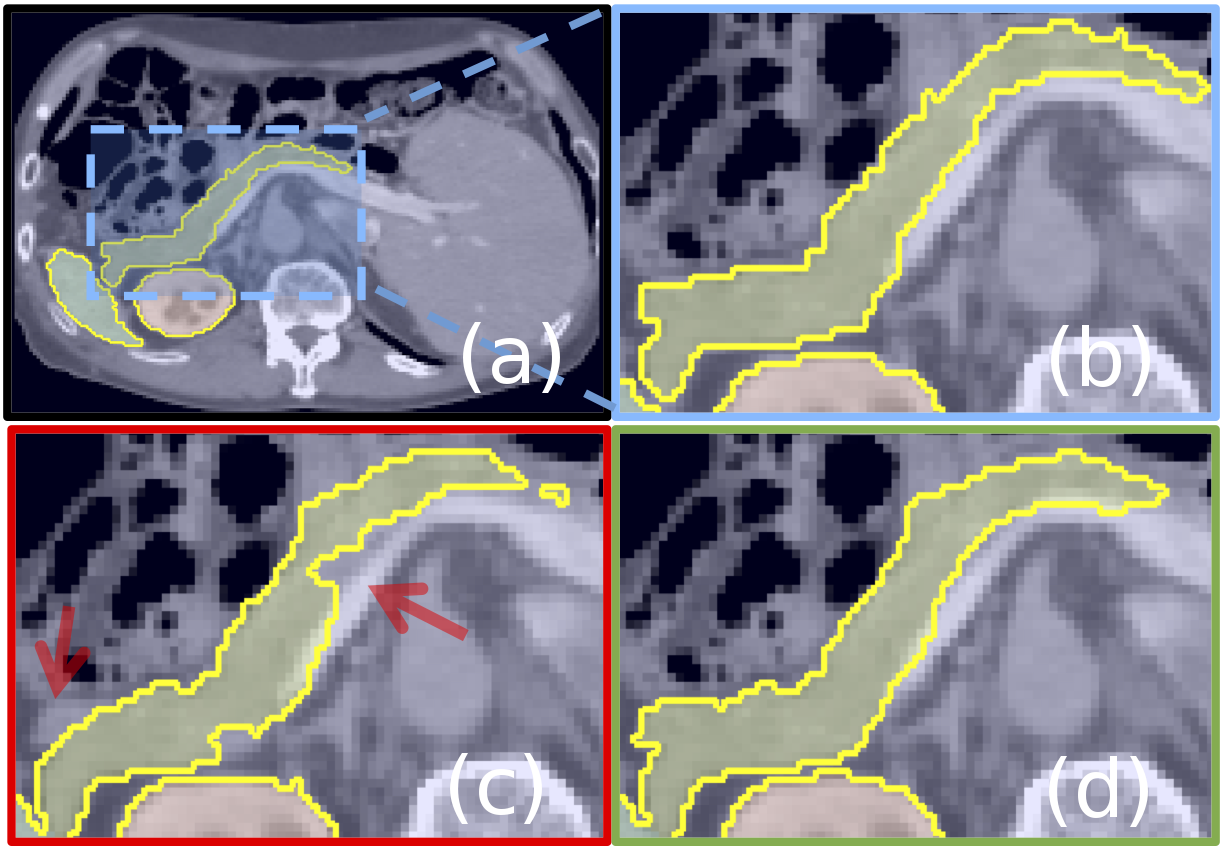

Segmentation Experiments: The proposed Attention U-Net model is benchmarked against the standard U-Net on multi-class abdominal CT segmentation. We use - dataset for both training () and testing (). The corresponding Dice scores (DSC) and surface distances (S2S) are given in Table 1. The results on pancreas predictions demonstrate that attention gates (AGs) increase recall values () by improving the modelβs expression power as it relies on AGs to localise foreground pixels. The difference between predictions obtained with these two models are qualitatively compared in Figure 2. In the second experiment, the same models are trained with fewer training images () to show that the performance improvement is consistent and significant for different sizes of training data (). For both approaches, we observe a performance drop on spleen DSC as the training size is reduced. The drop is less significant with the proposed framework. For kidney segmentation, the models achieve similar accuracy since the tissue contrast is higher.

Attention coefficients, , identify salient image regions and prune feature responses to preserve only the activations relevant to the specific task as shown in Figure 2. The output of AGs is the element-wise multiplication of input feature-maps and attention coefficients: . In a default setting, a single scalar attention value is computed for each pixel vector where corresponds to the number of feature-maps in layer . In case of multiple semantic classes, we propose to learn multi-dimensional attention coefficients. This is inspired by [29], where multi-dimensional attention coefficients are used to learn sentence embeddings. Thus, each AG learns to focus on a subset of target structures. As shown in Figure 2, a gating vector is used for each pixel to determine focus regions. The gating vector contains contextual information to prune lower-level feature responses as suggested in [32], which uses AGs for natural image classification.